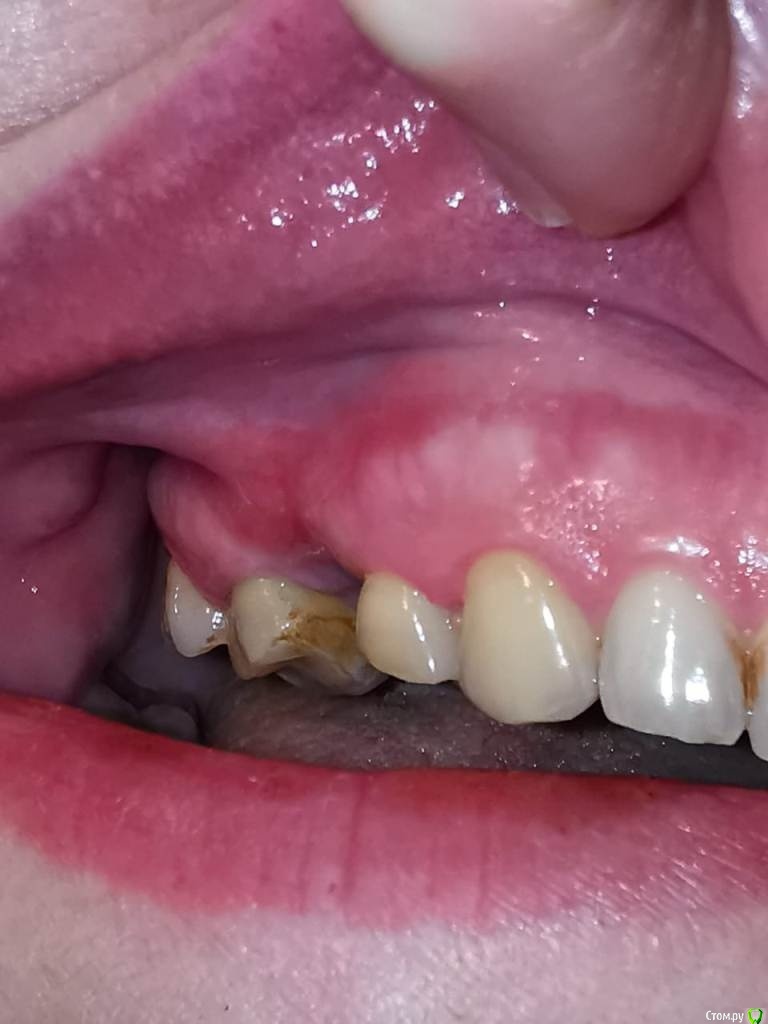

Tatiana72 Опубликовано 23 октября, 2020 Поделиться Опубликовано 23 октября, 2020 (изменено) Добрый день, уважаемые доктора! Заболело, как оно водится, именно тогда, когда были закрыты все стоматологические клиники из-за пандемии. Кое-как дотерпела до открытия и понеслась к своему доктору. В июне депульпировали и пролечили верхнюю правую четверку (1.4 если не ошибаюсь), в августе поставили имплант Астра вместо 1.5 зуба. Одновременно подчистили экзостоз над 1.5 под будущее протезирование. Доктор закрыл разрез, натянув слизистую сверху и сшил ее над имплантантом со слизистой с внутренней стороны. (фото не очень четкое, но видно полоску слизистой как раз над 1.5 зубом). Из-за этого сильно опустился тяж над 1.5 зубом. Через некоторое время после снятия швов меня стали беспокоить тупые, тянущие боли в районе 1.4-1.5 зубов, особенно по вечерам. При жевании ничего не чувствую, но если надкусить что-нибудь твердое или постучать по 1.4, то зуб будет ныть 4-5 минут. При физических нагрузках и прыжках тоже самое. Кость на месте убранного экзостоза тоже болезненна, прощупывается маленький бугорок. Мой доктор ничего не видит, хотя я жаловалась на боли неоднократно. Четверку удалять отказывается, говорит, что зуб хороший, планируется протезирование под коронку, а у меня уже сил нет, ноет каждый вечер, а иногда и сразу с утра. В чем может быть причина, с чего начать? Четверку уже очень хочется вырвать, чтобы не ныла, но есть сомнения, что проблема именно в ней. Изменено 23 октября, 2020 пользователем Tatiana72 Ссылка на комментарий

Tatiana72 Опубликовано 25 октября, 2020 Автор Поделиться Опубликовано 25 октября, 2020 (изменено) Спасибо. КТ сделаю на неделе, в выходные не получилось записаться, сразу выложу. А пока вопрос по десне, правильно ли провели операцию по натяжению слизистой Фото убрала в скрытый текст, не очень красиво выглядит. Видно опущенный тяж и участок красного цвета, который натянули над 15 зубом. Может это являться причиной боли? 14 зубом слегка задеваю за щеку, не травматично, но ощутимо. Зуб спереди подпиленный, а сзади остался как был. Изменено 25 октября, 2020 пользователем Tatiana72 Ссылка на комментарий